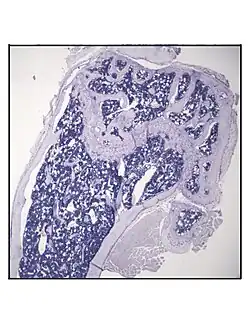

Bone marrow adipocytes are derived from mesenchymal stem cell (MSC) differentiation.

In order to understand the physiology of BMAT, various analytic methods have been applied. BMAds are difficult to isolate and quantify because they are interspersed with bony and hematopoietic elements. Until recently, qualitative measurements of BMAT have relied on bone histology,[51][52] which is subject to site selection bias and cannot adequately quantify the volume of fat in the marrow. Nevertheless, histological techniques and fixation make possible visualization of BMAT, quantification of BMAd size, and BMAT's association with the surrounding endosteum, milieu of cells, and secreted factors.[53][54][55]